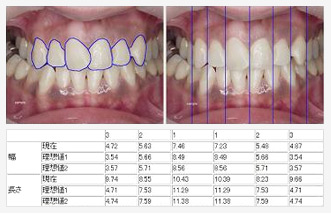

画像解析による、計算結果データ

国際特許取得済み当院が誇る「CGシミュレーション」システム、DRISにより"施術後のイメージ"お見せした上で、理想の微笑みづくりに取り組み、ご提供いたします。

- 治療前のクライアントの顔写真と口元の写真から、治療後をシミュレーションした画像を作成します。

- 理想的な歯のサイズ等の治療に必要なデータを計算、補綴物の作成をサポートします。